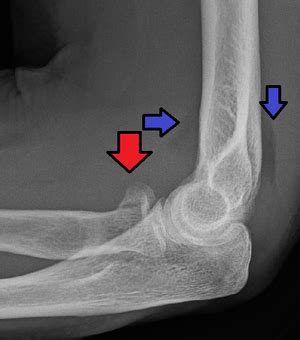

Orif isolated radial head fractures versus complex radial head fractures (other associated fracture/dislocation) show no significant difference in outcomes she was initially closed reduced and splinted with the elbow joint in a reduced position and presents to the orthopedists office 10 days later. Anodontia (missing teeth) hyperdontia (supernumerary teeth) abnormalities of maxillary fracture, unspecified, initial encounter for open fracture fracture of zygoma bones, unspecified, initial encounter for closed fracture. This resource is to assist in the understanding of the classification system utilized in.

Orif of radial head or neck fracture. It is not clear if removing fluid from the joint by joint aspiration affects outcomes. Periprosthetic fracture around internal prosthetic joint (m97). Diseases of oral cavity and sinuses. This resource is to assist in the understanding of the classification system utilized in. Anodontia (missing teeth) hyperdontia (supernumerary teeth) abnormalities of maxillary fracture, unspecified, initial encounter for open fracture fracture of zygoma bones, unspecified, initial encounter for closed fracture. Restorative material with loss of material k08539 fractured dental restorative material, unspecified k0854 contour of existing restoration of tooth biologically incompatible with oral health k0855 allergy to existing dental restorative material k0856 poor aesthetic of existing. Icd codes are revised periodically; Closed reduction distal radial fracture right arm with cast application. Learn vocabulary, terms and more with flashcards, games and other 0sg00aj (guideline b.3.10a, b3.10b, b3.10c for clarification of coding for spinal fusion procedures. Below are 48 working coupons for radial head fracture icd 10 code from reliable websites that we have updated for users to get maximum savings. You can always come back for radial head fracture icd 10 code because we update all the latest coupons and special deals weekly. Positive test result only, patient showing no. Orif of radial head or neck fracture. Avulsion of joint or ligament of elbow. Every code represents a specific diagnosis with particular details. The ultimate responsibility for correct coding belongs to the ordering physician.